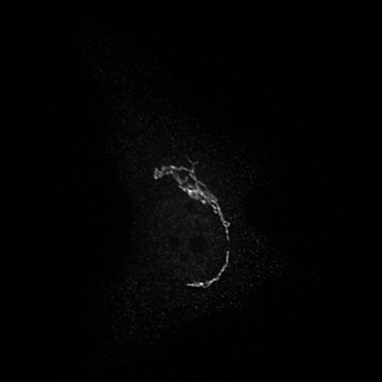

Microscopy techniques are employed to capture subcellular localization images of proteins in a cell, which were previously analyzed using traditional wet methods. However, advances in microscopy techniques have brought an avalanche of medical images in a considerable amount; hence, manual analysis and processing of these medical images become nearly impossible for biologists. Moreover, a subjective inspection of images may lead to errors in decision-making process shao2017deep ; tahir2011protein ; kreft2004automated . It is highly likely that the images generated for proteins of the same class may look visually different (see Figure 1). Similarly, proteins belonging to two different classes may look alike. Such a situation leads to the poor performance of classification systems. These problems are resolved by applying different hand-crafted feature extraction strategies to capture multiple views from the same image tahir2016protein . Hence, this is a cumbersome job and may fail to discriminate with high accuracy.

Prediction confidence: We compare the prediction confidence of traditional classifiers trained on Yeast and HeLa datasets against our PLCNN on four images as shown in Figure 11. Each image has the prediction probabilities for each algorithm underneath. The red color shows when the prediction is incorrect, whereas the green is for the correct outcome. It can be observed that our method predicts the correct labels with high confidence, while the probability is very low when the prediction is incorrect. The image in the first column in Figure 11 is very challenging due to minimum texture and almost no structure. All the methods failed to identify the type of protein in the mentioned image correctly. However, the competing methods prediction scores are much higher than ours. Similarly, our algorithm confidence is always high when the prediction is correct and low when it is incorrect. This shows the learning capability of our network.

![]() |

|

| AlexNet | 0.32 | 0.57 | 0.79 | 0.82 |

|---|---|---|---|---|

| ResNet | 0.69 | 0.68 | 0.49 | 1 |

| DenseNet | 0.60 | 0.79 | 0.75 | 0.90 |

| PLCNN | 0.26 | 0.88 | 1 | 1 |